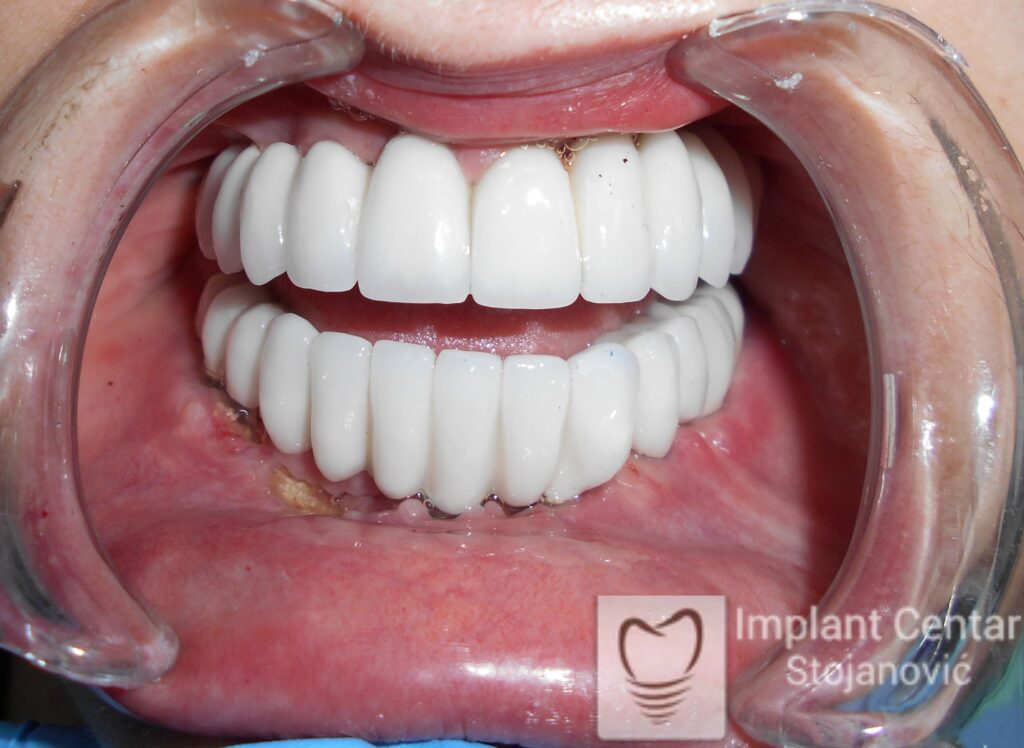

Pacijentkinja je došla sa dotrajalim mostovima i preostalim zubima loše biološke vrednosti, dok su bezubi prostori bili prisutni u gornjoj vilici sa desne strane i  u donjoj vilici sa leve strane. Nakon detaljnog kliničkog pregleda i analize snimaka, izvršeno je vađenje svih zuba i ugradnja optimalnog broja dentalnih implantata.

Već tri dana nakon operacije pacijentkinja je zbrinuta privremenim krunicama, kojima je bila oduševljena jer su odmah omogućile funkciju i estetiku. Nakon perioda oseointegracije izrađene su definitivne cirkonijum-keramičke krunice, čime je postignuta maksimalna estetika, funkcija i vraćeno samopouzdanje. Pacijentkinja je presrećna postignutim rezultatom.